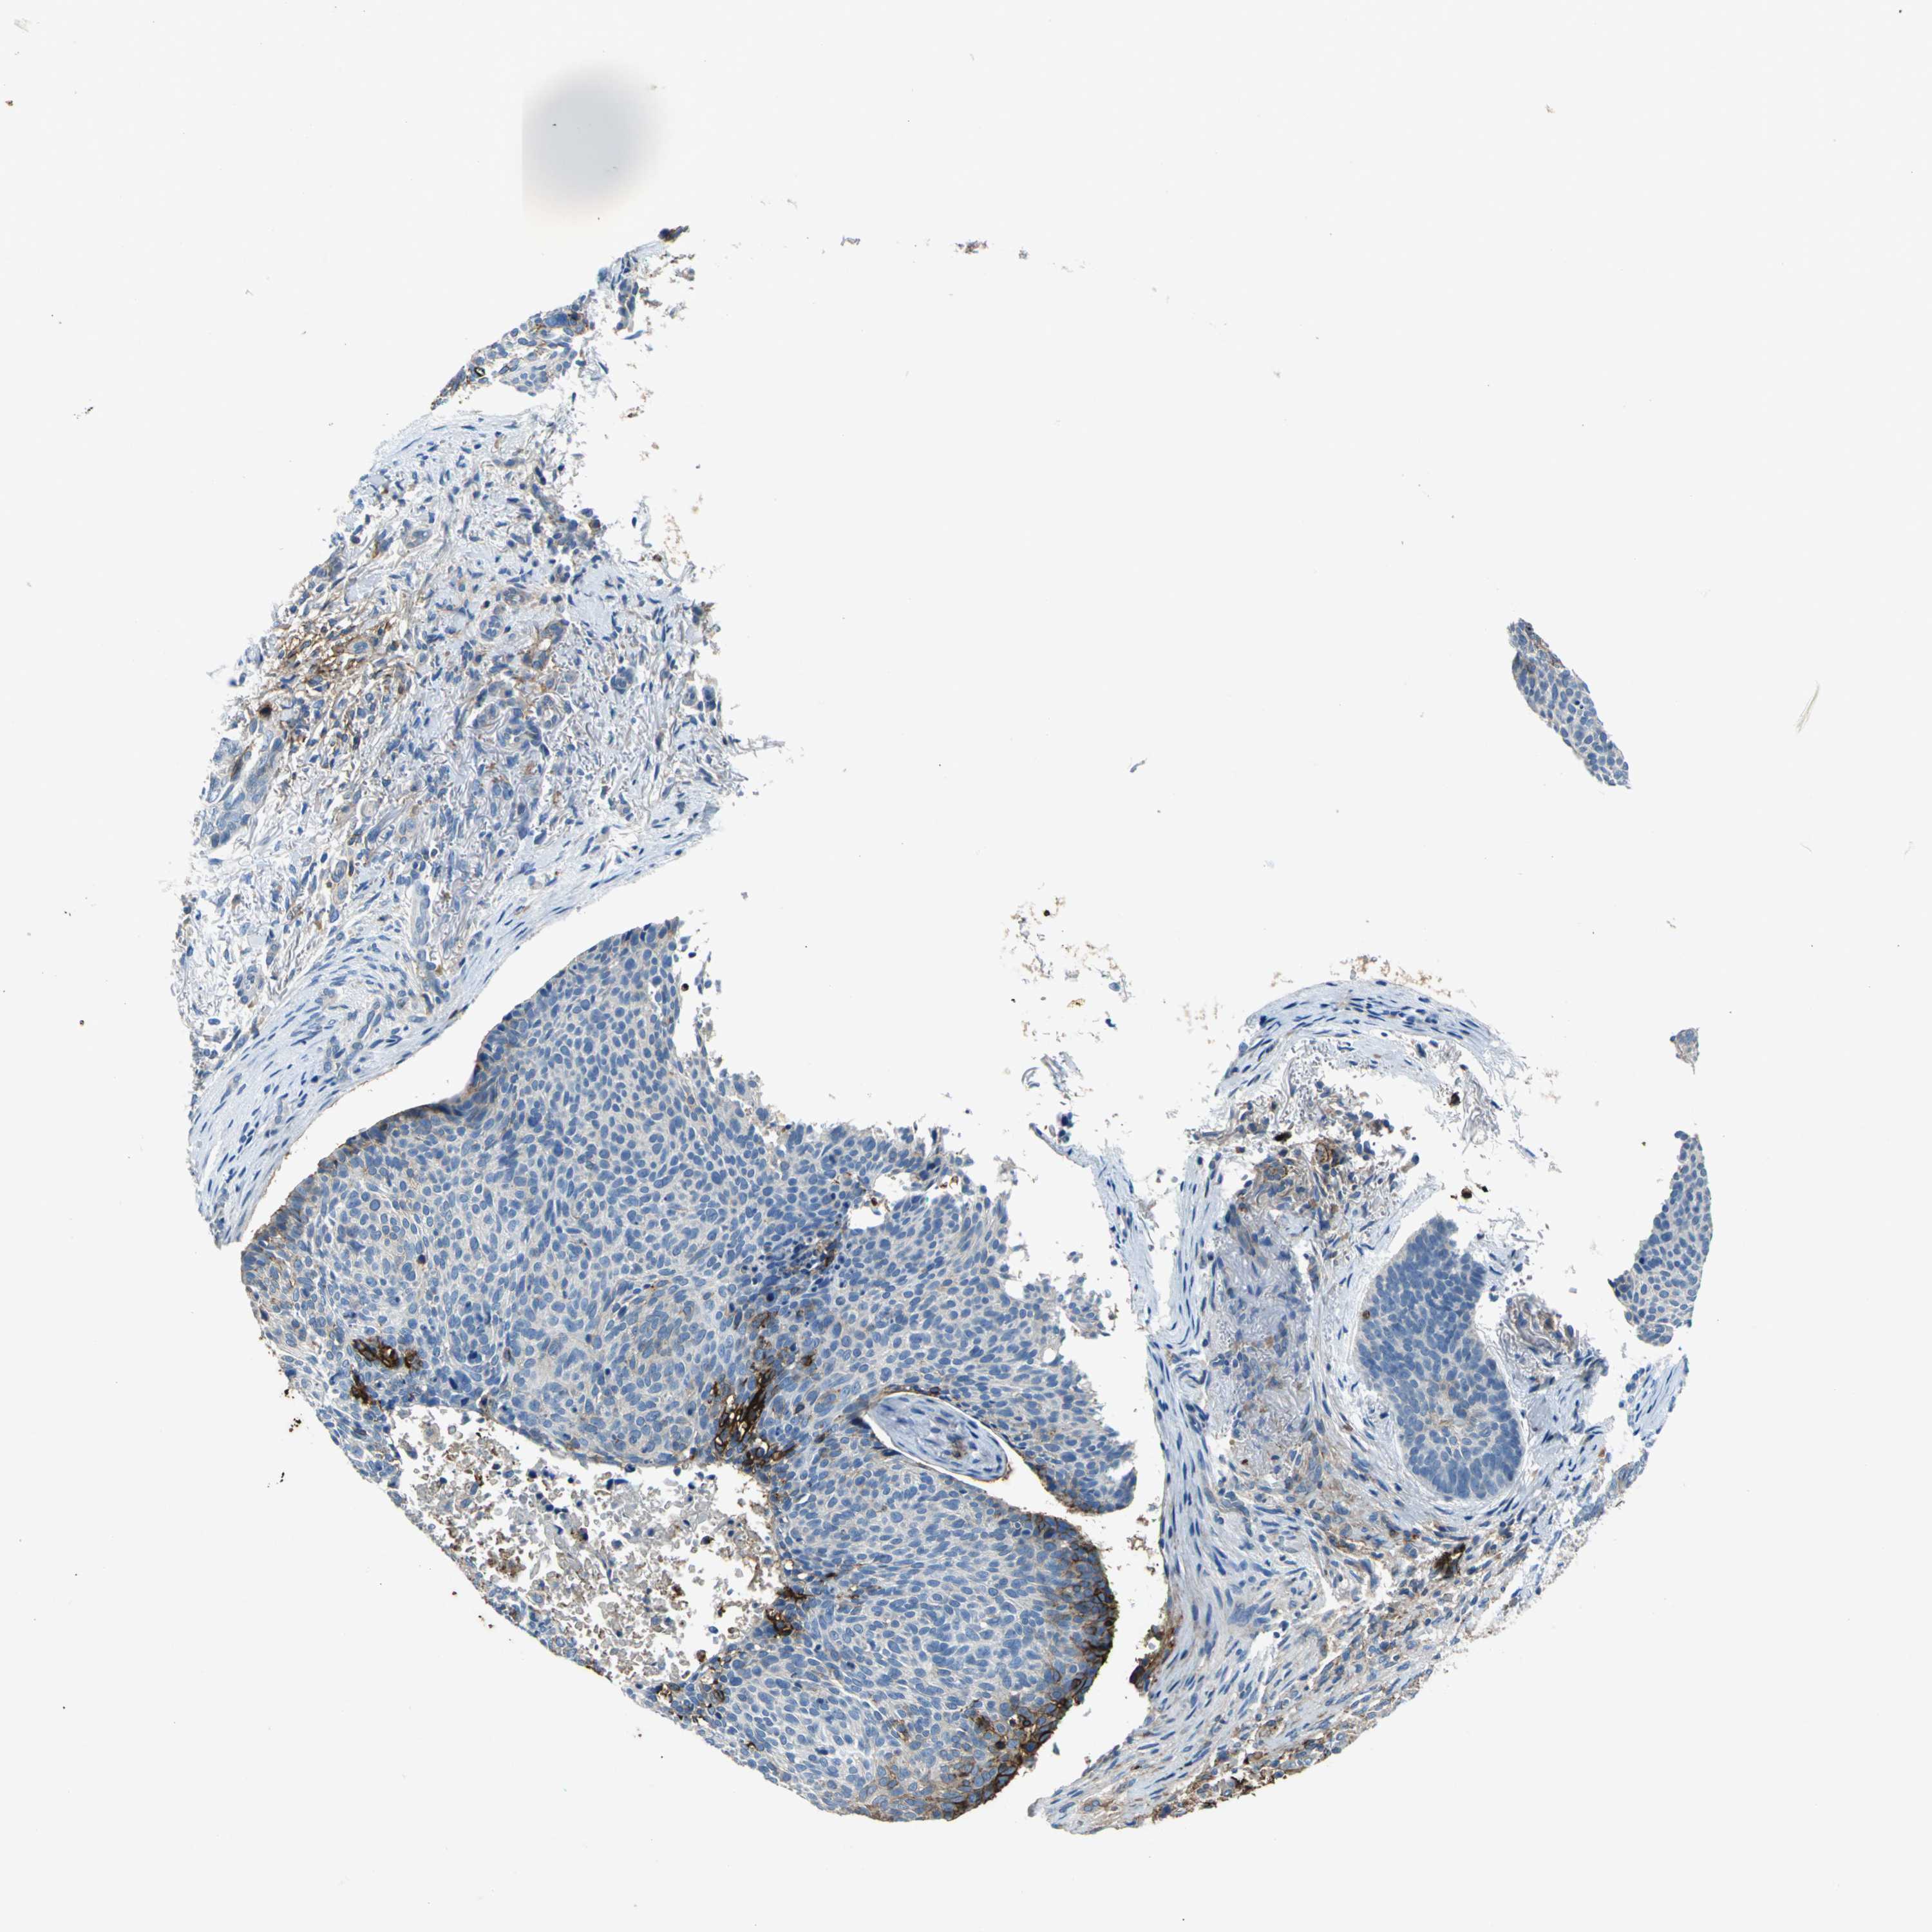

SKIN CANCER - Protein expressioni

A mouse-over function shows sample information and annotation data. Click on an image to view it in a full screen mode. Samples can be filtered based on level of antibody staining by selecting one or several of the following categories: high, medium, low and not detected. The assay and annotation is described here.

Antibody stainingi

Antibody staining in the annotated cell types in the current human tissue is reported as not detected, low, medium, or high, based on conventional immunohistochemistry profiling in selected tissues. This score is based on the combination of the staining intensity and fraction of stained cells.

Each image is clickable and will lead to virtual microscopy that enables deeper exploration of all samples and also displays staining intensity scores, fraction scores and subcellular localization as well as patient and tissue information for each sample.

Antibody HPA005985

Staining

High

Medium

Low

Not detected

Intensity

Strong

Moderate

Weak

Negative

Quantity

>75%

75%-25%

<25%

None

Location

Nuclear

Cytoplasmic/membranous

Cytoplasmic/membranous,nuclear

Squamous cell carcinoma, NOS